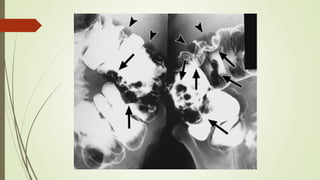

HERNIA OBTURATRIZ

 RADIOGRAFÍA DE ABDOMEN O ESTUDIOS

BARITADOS:

 Obstrucción del intestino delgado con un asa fija que

contiene gas o medio de contraste en la región del

obturador.

 HALLAZGOS DE TC:

 Asa de intestino que protruye a

través del agujero obturador.

 Frecuentemente:

 Asa ileal.

 Atrapada entre los músculos

obturador externo y pectíneo.

 Lado derecho.